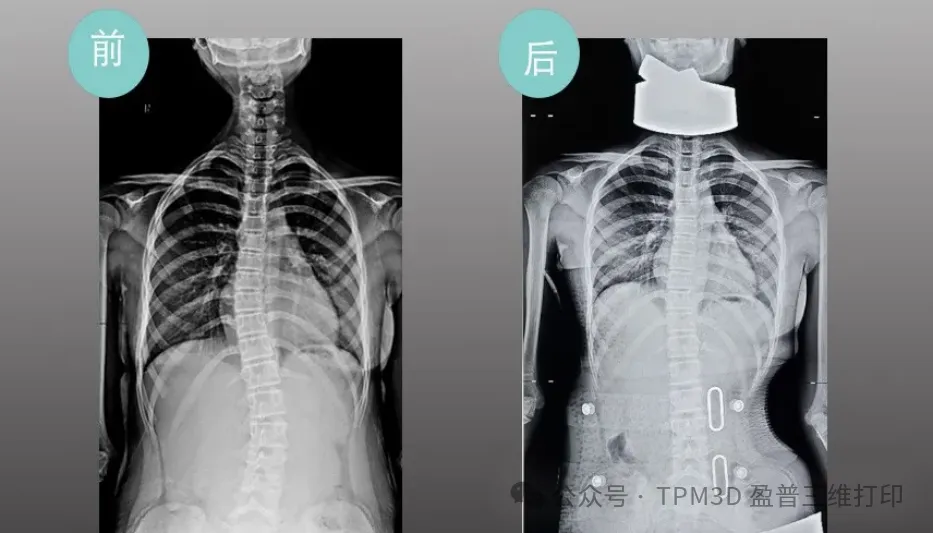

中心曾接診過這樣一位患者--五年級的小羅。當時,她因 25°脊柱側(cè)彎面臨治療困境,家庭經(jīng)濟壓力更讓她的矯正之路舉步維艱。得知情況后,盈普技術(shù)團隊與中心迅速聯(lián)動,為小羅定制了專屬的 3D 打印矯形支具。從數(shù)據(jù)采集、支具設(shè)計到打印成型,全程僅用很短時間便完成。

令人欣喜的是,小羅佩戴支具僅一周,脊柱側(cè)彎度數(shù)就從 25°降至 10°以內(nèi)。如今的她,身姿挺拔,重拾自信,家屬特意送來錦旗,上面 “仁心仁術(shù)治側(cè)彎”的話語,是對這份科技與醫(yī)療結(jié)合的溫暖最生動的注解。